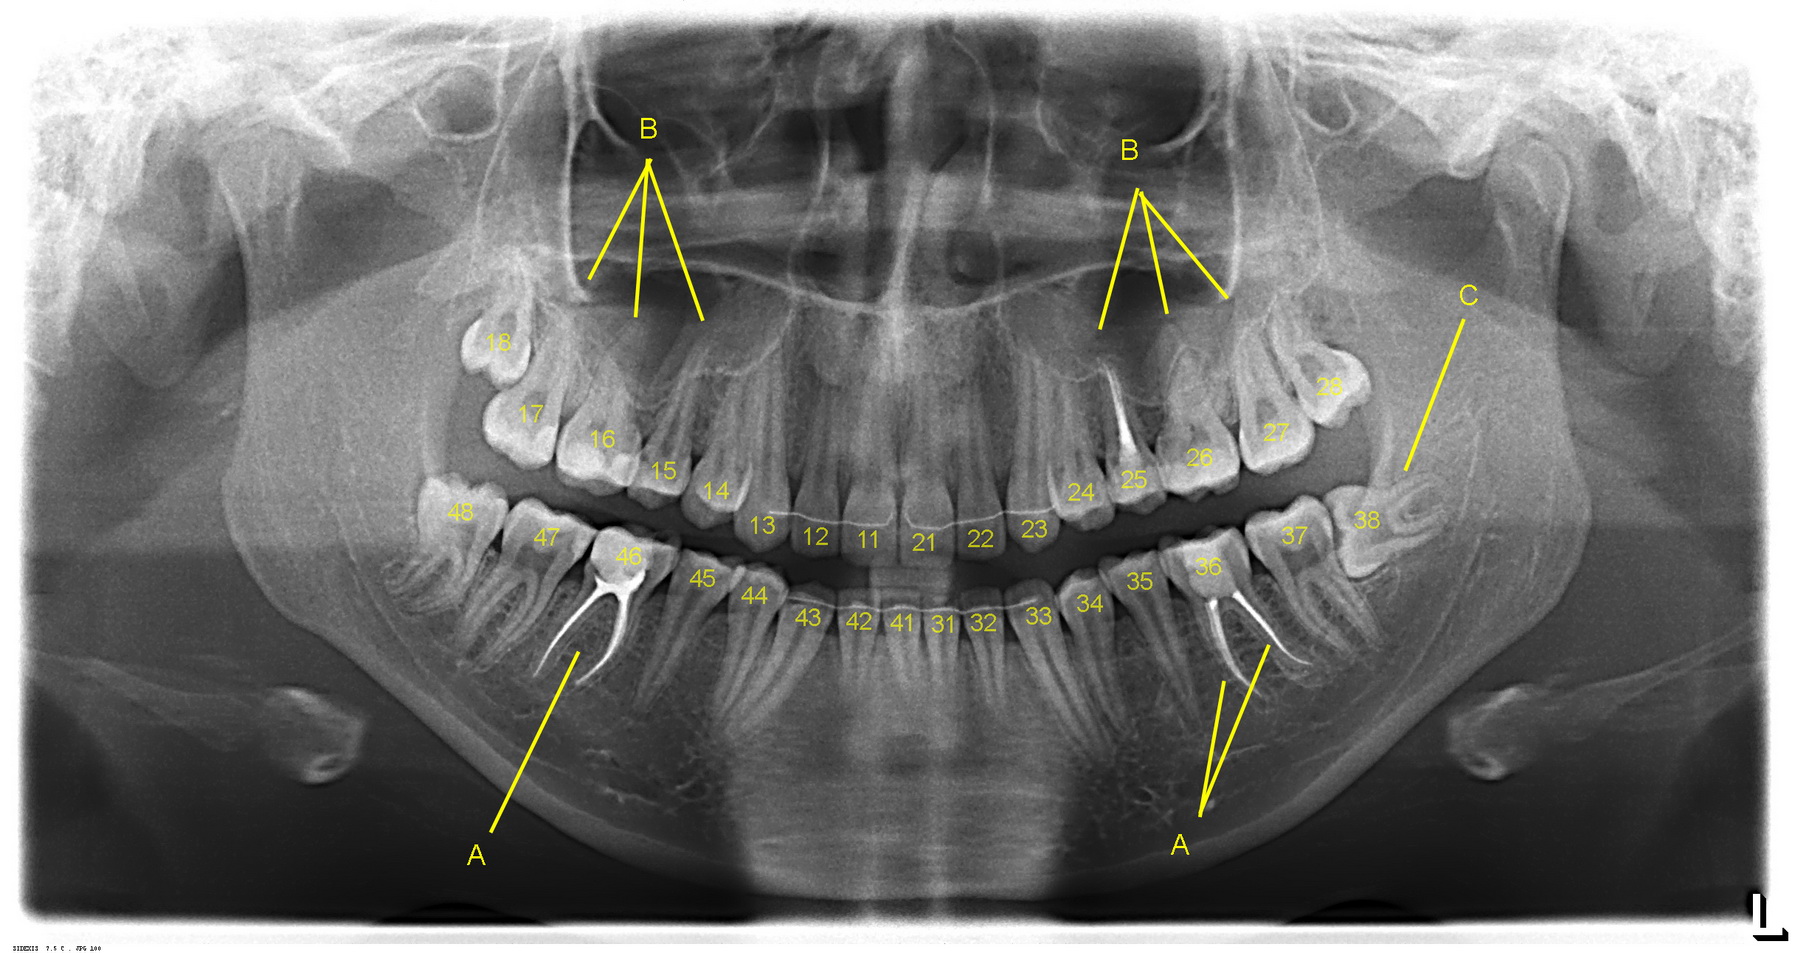

Если мы возьмём сегодняшнюю операцию удаления зуба, то из импортного в ней — только анестетик (который также легко заменяется российскими дженериками):